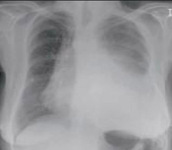

Radiografía de tórax que muestra una adenopatía hiliar bilateral en un paciente con sarcoidosis

De la colección personal del Dr. M.P. Muthiah, Departamento de Medicina Intensiva y Pulmonar y Medicina del Sueño, University of Tennessee